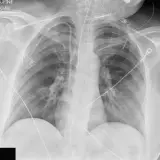

Over 2,100 interactive radiology cases, curated by radiologists for your level of training. Scroll, window, and view cases full screen — just like on PACS. Click linked findings in each writeup to jump straight to them on the image. Cases include sample reports, a focused discussion section, original illustrations, and videos.

Des cas entièrement interactifs avec les outils attendus d'un PACS — défilement, fenêtrage, zoom, déplacement, mesures, ROI et mode plein écran.

Des annotations détaillées mettent en évidence les résultats clés directement sur les cas. Cliquez sur les résultats liés dans les descriptions de cas pour accéder à leur emplacement exact sur l'examen.